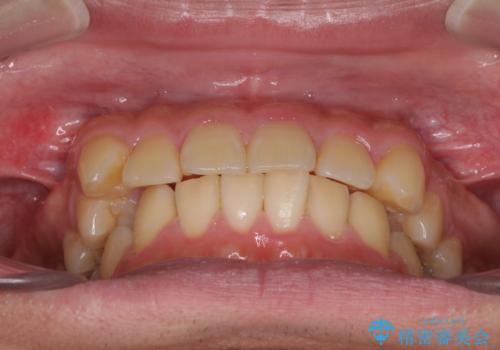

配属異動や長時間勤務などによりインビザラインが十分に装着できない期間があり、インビザライン有効期限5年間ギリギリとなってしまいました。